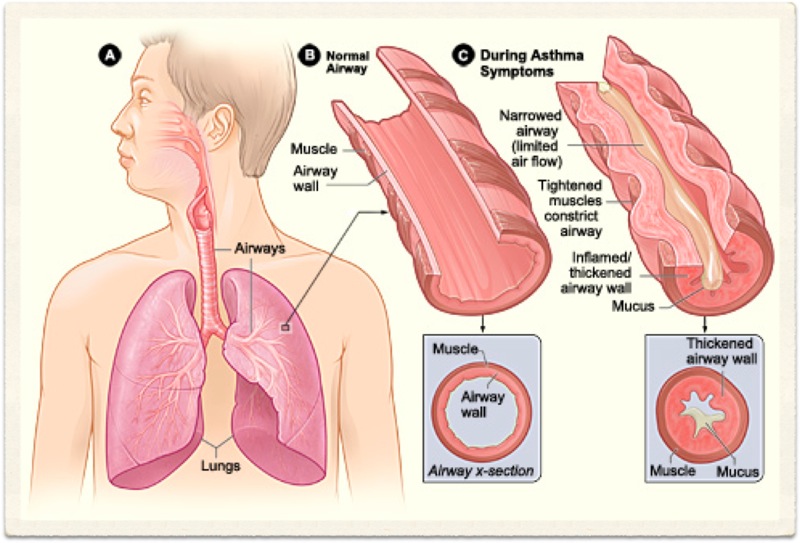

Chronic Obstructive Pulmonary Disease (COPD) is an 'umbrella' term for people with chronic bronchitis, emphysema, or both. With COPD the airflow to the lungs is restricted (obstructed). COPD is usually caused by smoking. Symptoms include cough and breathlessness.

Chronic bronchitis cannot be diagnosed radiologically. Although findings such as increased lung markings or tubular opacities, bronchial wall cuffing (thickening) can be seen with bronchitis, they are nonspecific. The main reason for getting a chest X-ray is to exclude other conditions, such as bronchiectasis, which can mimic the disease clinically.